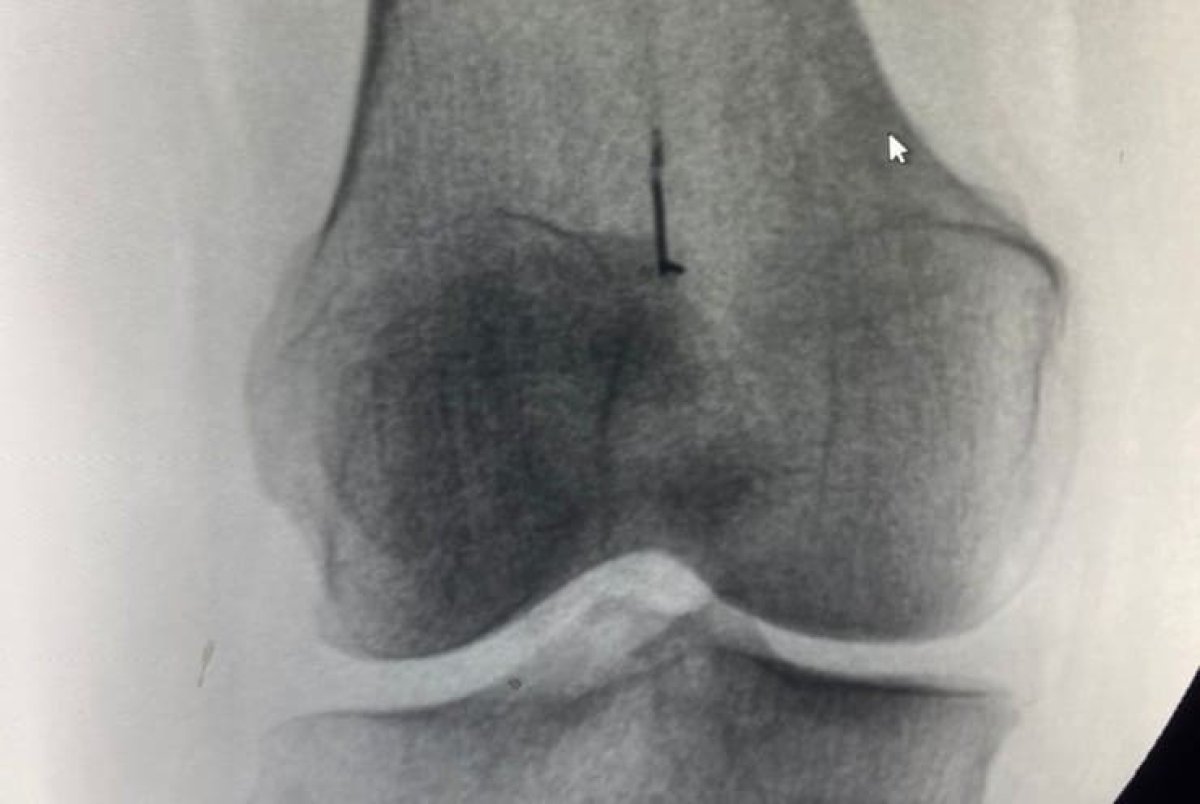

Женщина получила травму еще в детстве, а потом всю сознательную жизнь в правом коленном суставе "носила" иглу от швейной машины. К врачам она обратилась в момент, когда появилась хромота, пишет Tengrinews.kz

Травматологи ЦГКБ провели операцию по удалению инородного тела. Специалистам понадобилось около получаса, чтобы избавить женщину от необычной ноши. Оперирующий травматолог Даулет Чукманов отметил, что за много лет металлический предмет инкапсулировался, то есть оброс соединительной тканью. Отмечается, что после операции женщина перестала хромать, боль исчезла.